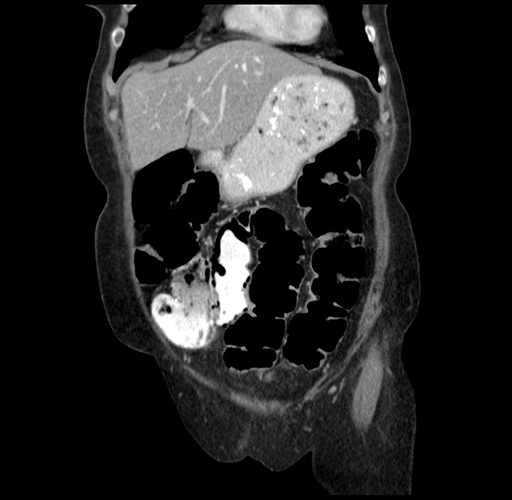

Pre-Chemo: Coronal Venous

Coronal Venous